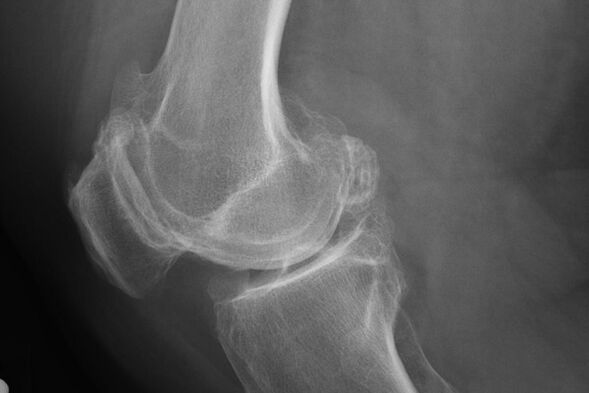

X -ray membantu mengenal pasti penyimpangan dalam tulang rawan.

Selepas peperiksaan, doktor menetapkan radiografi pesakit. Ini adalah kaedah utama untuk mendiagnosis osteoarthritis sendi lutut dari mana -mana darjah.

X -ray memberikan Doktor idea tentang perubahan dalam tulang rawan sendi. Walau bagaimanapun, dalam beberapa kes, fasa awal tidak dapat ditakrifkan dalam gambar.

Sekiranya perlu, doktor boleh menetapkan laluan berulang dari pencitraan resonans X-ray atau aritmetik dan magnetik.